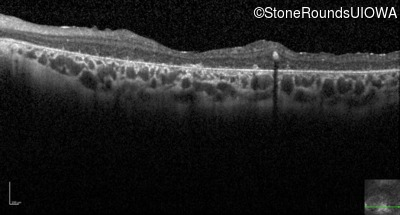

Optical Coherence Tomography - Right - 20/400 sc

Exemplar / OCT Stack